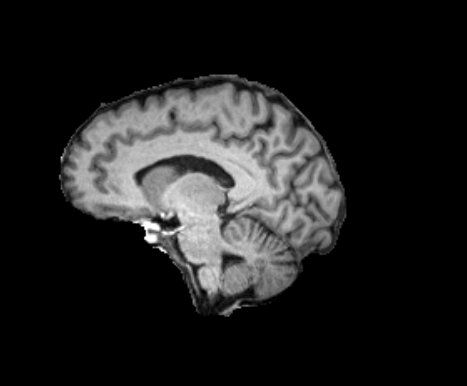

3.1.2 Segmentation

We used SynthSeg [6] (with the --parc option) to quickly (in less than a minute) produce FreeSurfer-like segmentations of the moving and reference images into 98 anatomical regions following the Desikan–Killiany–Tourville (DKT) protocol depicted in [39, 17]. For evaluation purposes, we grouped the labels into three anatomical groups: sub-cortical (labels: 10, 11, 12, 13, 17, 18, 26, 28, 49, 50, 51, 52, 53, 54, 58 and 60), cortical (labels greater than 1000) and white matter (super labels 2 and 41). When computing metrics for these groups, we report the average over the individual labels within each group, without merging the regions into a single aggregated label.